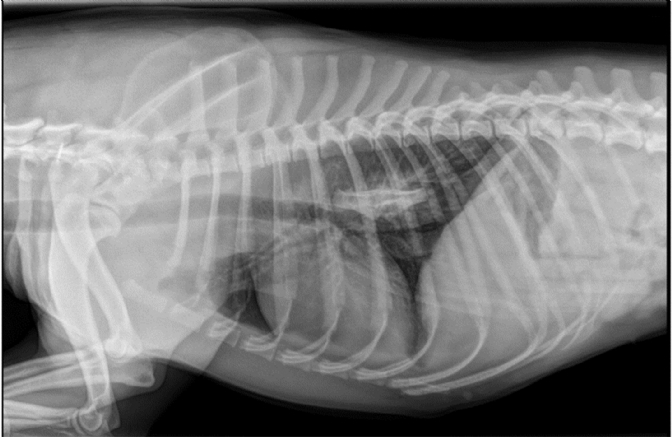

Jeudi 2 Mai 2019 Animaux de compagnieUne radiographie thoracique est réalisée en première intention.

Une chienne Staffordshire bull terrier de 5 ans est présentée pour un abattement, une dysorexie et deux épisodes de vomissements évoluant depuis 24 heures. A chaque prise de boisson, des régurgitations sont observées. La chienne a ingéré un os ...